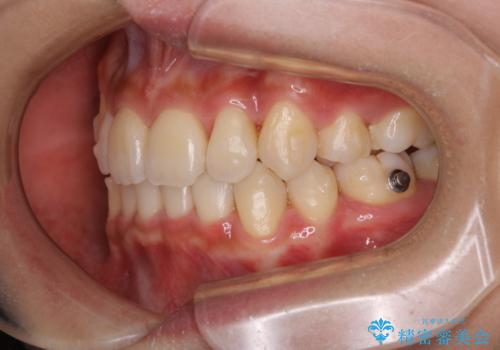

- 元々は海外でワイヤー矯正を行っていたが、コロナ禍で海外への往来が難しくなり、治療を中断せざるを得なくなってしまった方です。

ご本人のご希望により、インビザラインによる治療を行いました。

ブラケット除去直後に目立っていた下顎前歯部の大きなブラックトライアングルもあまり目立たなくなり、大変喜んでいただけました。